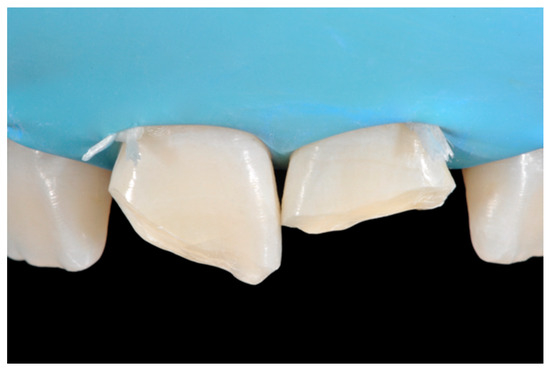

2.1.3. Completion of the Layering Procedure, Finishing and Polishing

A single shade of dentin (Clearfil Majesty ES-2, A1D, Kuraray Noritake Dental, Tokyo, Japan) was then applied placing separate increments (Figure 10 and Figure 11) to build the dentinal body, leaving space for incisal translucencies. The translucent shade (Clearfil Majesty ES-2, A1E, Kuraray Noritake Dental, Tokyo, Japan) was then applied to complete the restoration (Figure 12).

Finishing and polishing procedures were performed with a diamond bur (WL 268 014 Horico, Berlin, Germany), silicone points (Identoflex, Kerr, Bioggio, Switzerland) brushes (Jiffy Goat Air Brushes, Ultradent Products, South Jordan, UT, USA), and diamond pastes (Diamond Polish Mint, Ultradent Products, South Jordan, UT, USA) (Figure 13 and Figure 14). Satisfactory clinical and radiographic outcome was considered satisfactory at 3-months, 1-year, and 5-years post-operative (Figure 15, Figure 16, Figure 17, Figure 18 and Figure 19).